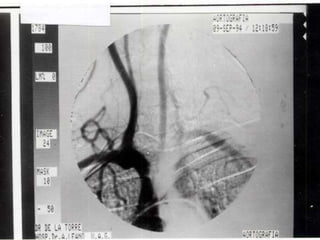

Cateterismo cardiaco: En casos atípicos o con lesiones asociadas El aortograma se realiza en proyección OIA Un gradiente de  40mmHg   ó más es significativo Determina circulación colateral

Cateterismo cardiaco: Encasos atípicos o con lesiones asociadas El aortograma se realiza en proyección OIA Un gradiente de 40mmHg ó más es significativo Determina circulación colateral